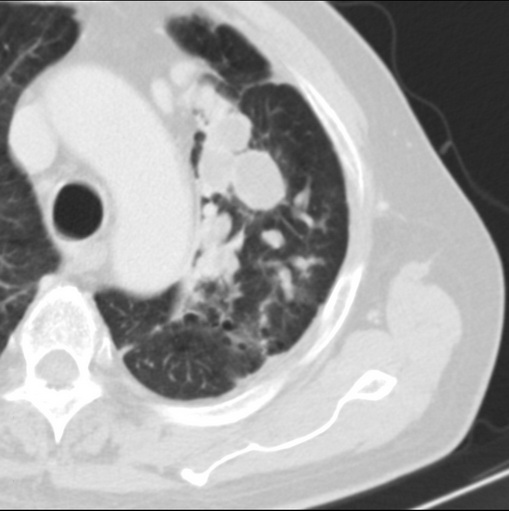

标题: CT25434:胸部CT增强扫描

男性患者 81岁 咳嗽 咳痰 咯血

左肺中心型肺癌并:1.左肺阻塞性肺炎;2.纵隔淋巴结肿大;

考虑左上肺癌并阻塞性肺炎,左肺转移、左肺门及纵隔淋巴结转移。

肿块贴近左肺门,包绕左上肺动脉,形态不规则。肿块增强扫描中度强化。纵膈内主动脉弓左旁间隙、气管隆突前、下间隙见多枚淋巴结影。综上考虑左侧中央型肺癌可能性大。图片没有完整上传,尤其是左肺上叶支气管分支层面没有上传,因此不好判断是叶支气管中断还是段支气管中断。另外,下图红色部分所示是“黏液支气管征”吗?